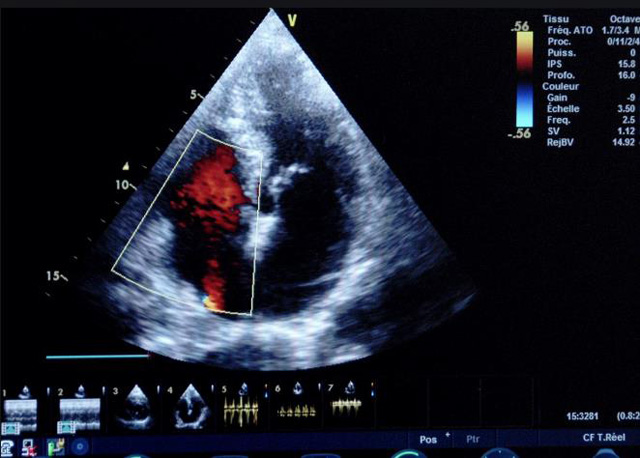

二、彩色室壁運動分析

(一)基本原理彩色室璧運動分析,從整體散射數(shù)據(jù)中識別心內(nèi)膜邊界,并與前一幀彩色不同,心臟收縮或舒張期開始到結(jié)束時心內(nèi)膜的全部過程。每一次順序顯示結(jié)束后,原來的彩色自動消失,以便進入下一個顯示過程。其結(jié)果是獲得對應(yīng)于每一個心動周期的彩色顯示,描繪特定周期內(nèi)室壁運動的時間運動軌跡。

(二)操作步驟根據(jù)背向散射數(shù)據(jù)中將心內(nèi)膜運動的位移過程分類為組織或血液的原理,邊緣檢測跟蹤心內(nèi)膜和血液的界面。橙色表示收縮期的開始,收縮期不同時相逐幀顯示色彩均疊加在收縮末期最后一幀圖像中。檢查時,可按以下步驟進行:

①顯示較為理想的二維圖像,常用切面有心尖四腔心、二腔心、左心室長軸和左心室乳頭肌水平短軸切面。

③啟動CK系統(tǒng),啟動后劃定感興趣區(qū)域。同時記錄的心動圖R波頂點為舒張末期,T波終點為收縮末期,顯示RT間期的CK彩階圖,連續(xù)記錄3~ 5個心動周期。

(三)檢測節(jié)段性室壁運動異常,研究冠心病患者左心室功能和分析局部室壁運動過程中。測量每一節(jié)段室壁的運動量,運動正常的節(jié)段彩帶色彩均勻?qū)哟喂庹_\動減弱的節(jié)段,厚度薄層次不全。心內(nèi)膜位移幅度和速度均減低。心內(nèi)膜位移幅度和速度甚低或難以測得。正常的多層彩帶消失,呈現(xiàn)紅色色帶,心內(nèi)膜位移呈負向,幅度和速度亦減低。急性心肌梗死的患者中可用于識別存活心肌抑或壞死心肌。多巴酚丁胺負荷試驗存活心肌的心內(nèi)膜位移幅度增高,停藥后即消失,而壞死心肌則無上述表現(xiàn)。實時檢查冠心病的節(jié)段性室壁運動異常,有時候通過發(fā)現(xiàn)局部心肌運動的時相異常,對于心臟傳導(dǎo)障礙的診斷也可能有幫助。